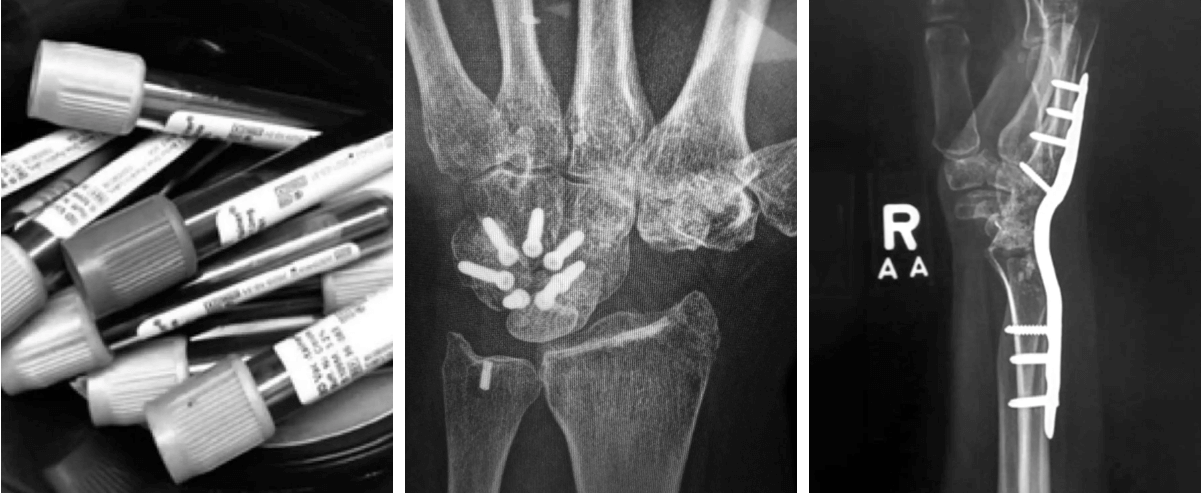

![Từ trái sang phải: Những bức ảnh ghi lại một số hành trình chữa bệnh của bà Lesley Yates sau những biến chứng do toa thuốc Cipro. Hành trình đó bao gồm xét nghiệm máu tổng quát để chẩn đoán tình trạng bệnh, phẫu thuật cổ tay phải vào năm 2014 để cố định [xương] và phẫu thuật cổ tay trái do gân và dây chằng bị rách vào năm 2018. (Ảnh: Được phép của bà Lesley Yates)](/wp-content/uploads/2024/03/special-post-2603SK18PM9.png)

Chín năm sau khi dùng các loại thuốc kháng sinh này, bà Yates vẫn phải chiến đấu với tình trạng đứt gân tiếp diễn dẫn đến tàn tật và đau đớn dai dẳng. Hành trình đầy mệt mỏi của bà – gặp vô số bác sĩ chuyên khoa và trải qua nhiều phương pháp điều trị khác nhau, từ vật lý trị liệu đến châm cứu mà không thấy thuyên giảm – làm nổi bật sự bất lực của hệ thống chăm sóc sức khỏe trong việc điều trị tác hại của fluoroquinolone.